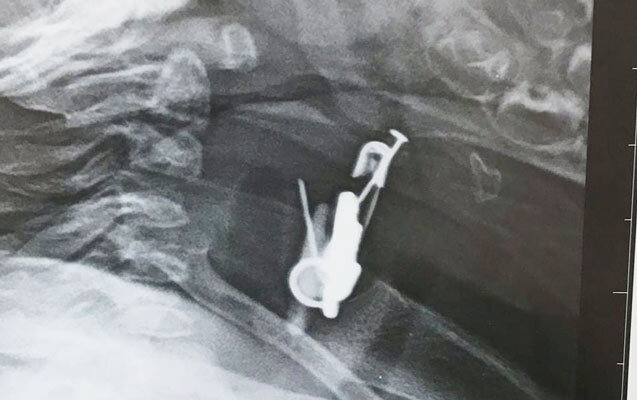

Valideyn tərəfindən Bakıya xəstəxanaya çatdırılan uşağın mədəsində yad cismin olduğu məlum olub. Belə ki, altı aylıq körpə sancağı və üzərində olan digər əşyaları udub. Ə.F.Qarayev adına 2 saylı uşaq kliniki xəstəxanasında endoskopik üsul ilə körpənin mədəsindən həmin əşyalar çıxarılıb.

Körpənin yaxınlarının verdiyi məlumata görə, uşağın hazırda vəziyyəti kafidir və müalicəsi davam etdirilir.